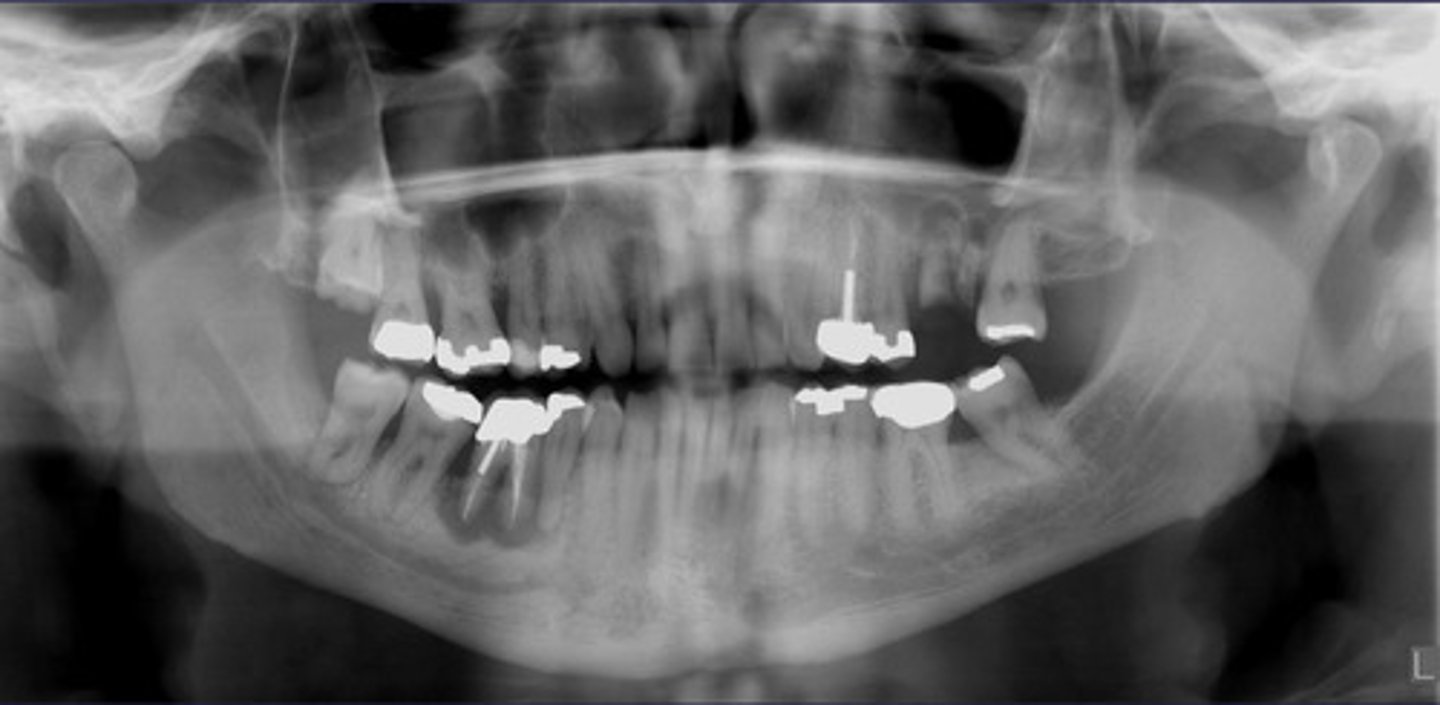

How would you describe the lesion?

- Periapical radiolucency associated with #30

- Has a band of sclerotic change extending from the apical radiolucency to the inferior alveolar canal and beyond

- Furcation involvement

(Furcation involvement as well as a band of sclerotic change extending from the apical radiolucency to the inferior alveolar canal and beyond)

What category would you put this lesion into?

Inflammation

what could be a differential diagnosis for this lesion? (select all that apply)

A. PCOD

B. multiple myeloma

C. apical rarefying osteitis

D. chronic sclerosing osteomyelitis

Also note apical rarefying osteitis #14 ( remnant root fragments, no crown due to caries)